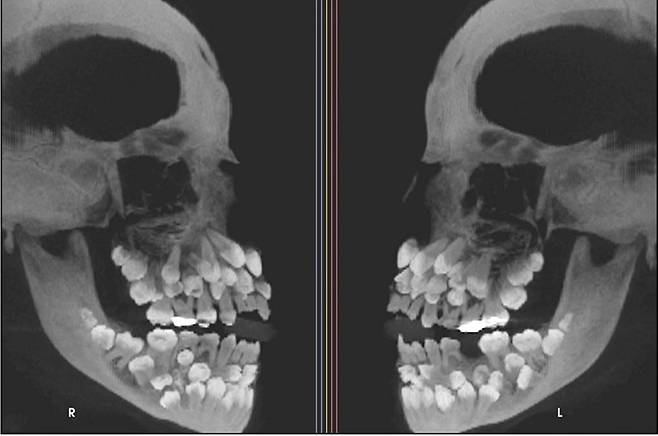

11세 소녀 입 안에서 치아가 무려 81개나 발견돼 학계에 충격을 안겼다.

최근 VN익스프레스 등 외신에 따르면 브라질에 사는 11세 소녀가 위쪽 유치 1개를 뽑기 위해 병원을 찾았는데 엑스레이 촬영 결과 소녀의 입안에서 유치 18개와 영구치 32개, 과잉치 31개 등 총 81개 치아가 발견됐다.

![브라질 한 10대 소녀에게서 81개 치아가 발견됐다. [VN익스프레스]](https://img4.daumcdn.net/thumb/R658x0.q70/?fname=https://t1.daumcdn.net/news/202507/17/ned/20250717083910096slxf.jpg)

이러한 상태는 ‘다발성 과잉치증(multiple hyperdontia)’으로 일반적으로 성인 기준 32개인 정상 치아 수를 넘는 추가 치아가 다수 존재하는 선천성 이상이다. 보통은 1~2개의 과잉치만 발견되는 경우가 많지만 이처럼 30개가 넘는 과잉치가 확인된 사례는 전 세계적으로도 매우 드물다.